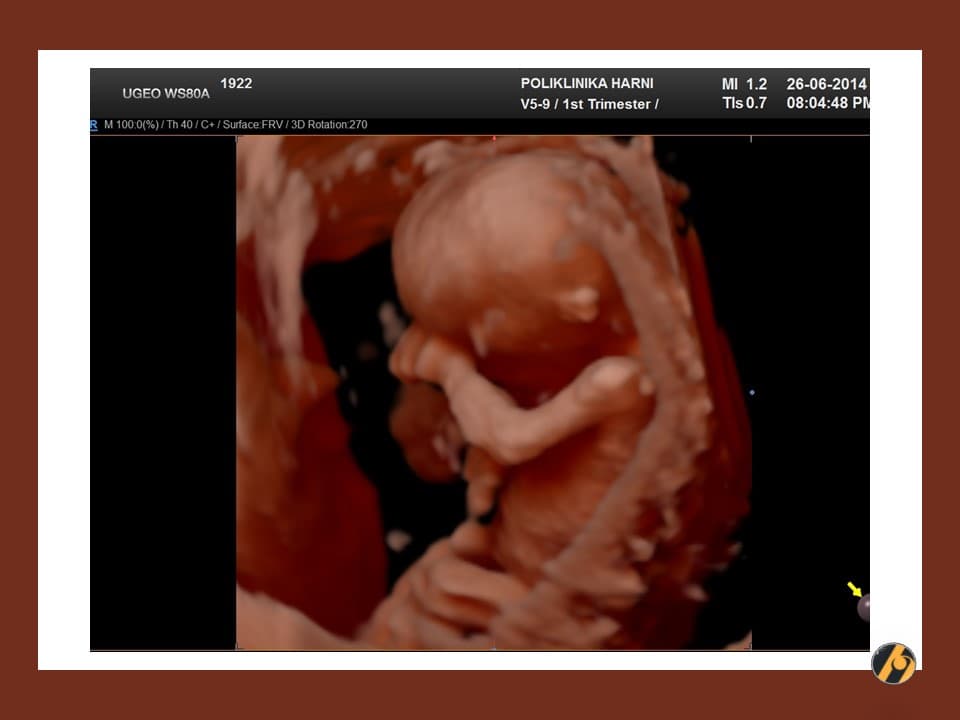

Glava vaše bebe još uvijek svojom veličinom nadmašuje tijelo, i čini gotovo cijelu polovicu dužine tijela. Razlog tomu je veoma rani početak razvitka mozga. Sada se uši postupno premještaju od vrata prema njihovom mjestu na glavi.

Napreduje razvitak ostalih organa. U trbuhu se intenzivno razvijaju crijeva, koja se nerijetko mogu vidjeti ultrazvučno i u pupčanoj vrpci / fiziološka omfalokela što je za ovaj period embriogeneze sasvim u redu. Crijeva se tijekom narednog tjedna vraćaju sasvim na svoje mjesto, u trbuh.

Razvija se mišićni sloj stijenke crijeva, koja stoga pokazuju peristaltiku - valove kontrakcija koji potiskuju hranu kroz crijevo. Dovršava se razvitak vanjskog spolovila vaše bebe.

Vaša beba dugačka je 4.5 - 6.0 cm, a teška je 8 - 10 g.